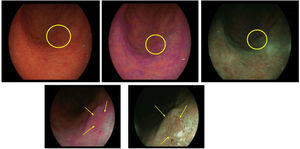

En la figura 1 se muestra un ejemplo de delimitación de los márgenes de un CGP con IC.

Neoplasia gástrica precoz antral de 11×9mm (círculo amarillo) en visión lejana. Cromoendoscopia con índigo-carmín (izquierda). En visión cercana se observa nítidamente la irregularidad del patrón glandular superficial en el interior de la línea de demarcación (flechas amarillas) (derecha).